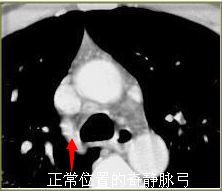

深圳小伙右肺突然不见 左肺差点也没了_报料_